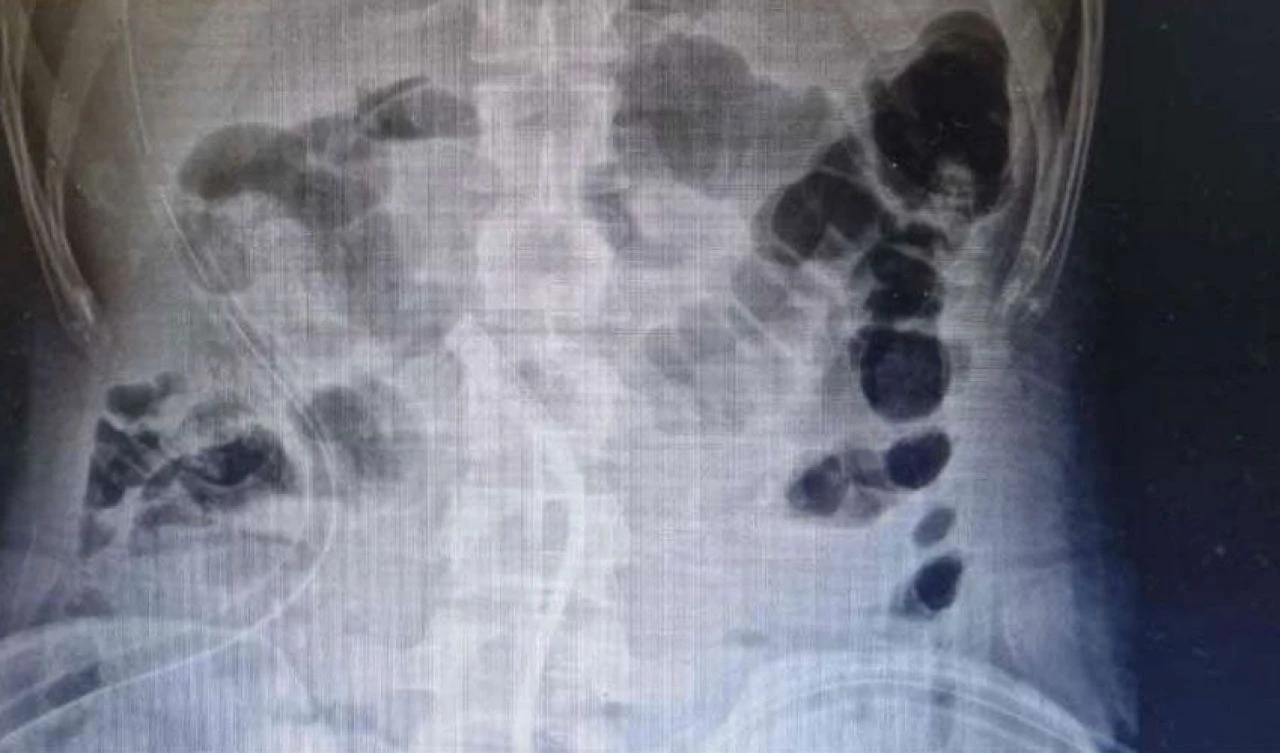

Doktorlar, genci ameliyata aldılar. Ameliyatta, mıknatısların ve madeni paraların ince bağırsakta iki ayrı halka halinde bir araya toplandığını, manyetik kuvvetin onları kilitleyerek bağırsak duvarı boyunca erozyona neden olduğu ortaya çıktı.

Ameliyat başarılı geçti ve gencin 39 bozuk para ve 37 mıknatıs çıkarıldı. Genç, 7 gün daha hastanede tutulmasının ardından taburcu edildi.